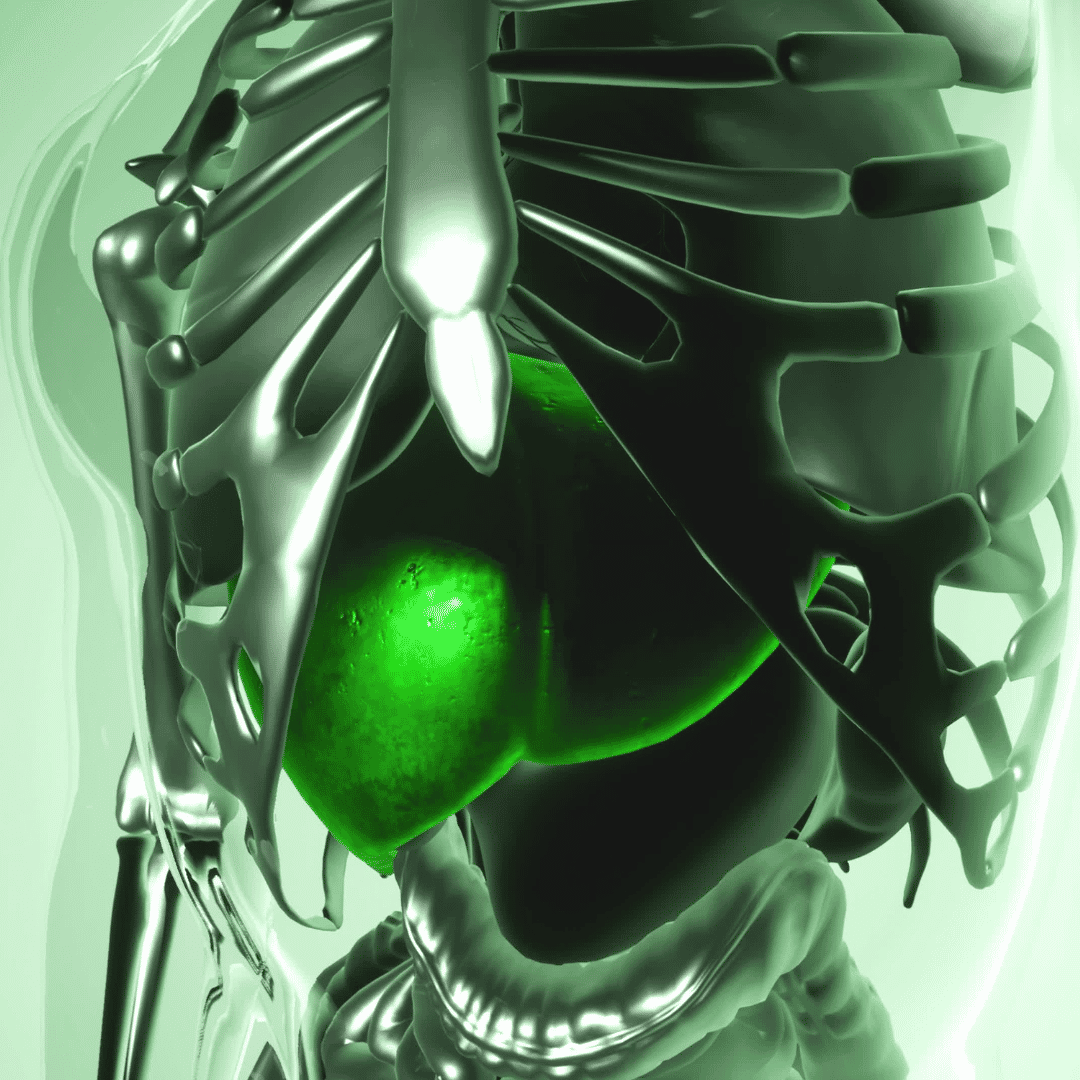

Gallbladder removal surgery otherwise known as a Cholecystectomy is one of the most common procedures to treat gallstones. The gallbladder is a pear-shaped organ that rests beneath the right side of the liver. Its main purpose is to collect and concentrate a digestive liquid (bile) produced by the liver. This procedure is a common treatment for symptomatic gallstones and other gallbladder conditions. When it is carried out, it will relieve pain, treat infection, and, in most cases, stop gallstones from coming back. Mexico is one of the best destinations to consider for affordable and high-quality Gallbladder Surgery.